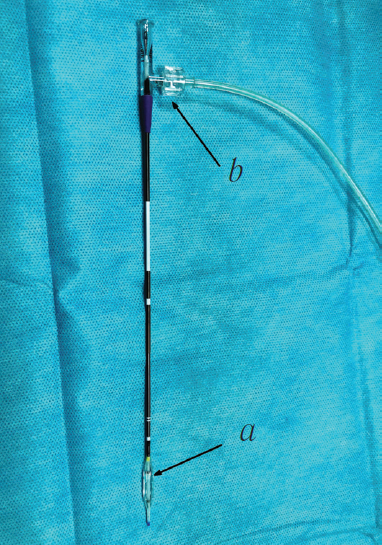

All patients underwent endonasal balloon dacryoplasty using a 6-mm balloon (Acclarent Inc., USA; Fig. 1). The length of the working part of the balloon was 16 mm and diameter 2.2 mm, and after inflation, it was 6 mm. A luer lock fastening was in place in the proximal part of the balloon for connection to the indeflator.

Fig. 1. Photo of a balloon catheter of 6 mm diameter in inflated state (Acclaren Inc., USA): a – active part of the balloon catheter; b – Luer-lock for connection with the indeflator

Рис. 1. Внешний вид баллонного катетера диаметром 6 мм в раздутом состоянии (Acclarent Inc., США): a — активная часть баллонного катетера; b — крепление типа Luer-lock для соединения с индефлятором